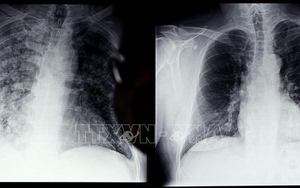

Tác động của Covid-19 đối với chức năng phổi của người trẻ

Đã có nhiều báo cáo về tình trạng giảm khả năng khuếch tán trong chức năng của phổi ở những bệnh nhân COVID-19 thể nặng và điều này góp phần gây ra một số triệu chứng nghiêm trọng liên quan đến COVID-19. Hơn nữa, phần lớn bệnh nhân nhập viện do COVID-19 bị suy giảm chức năng phổi.